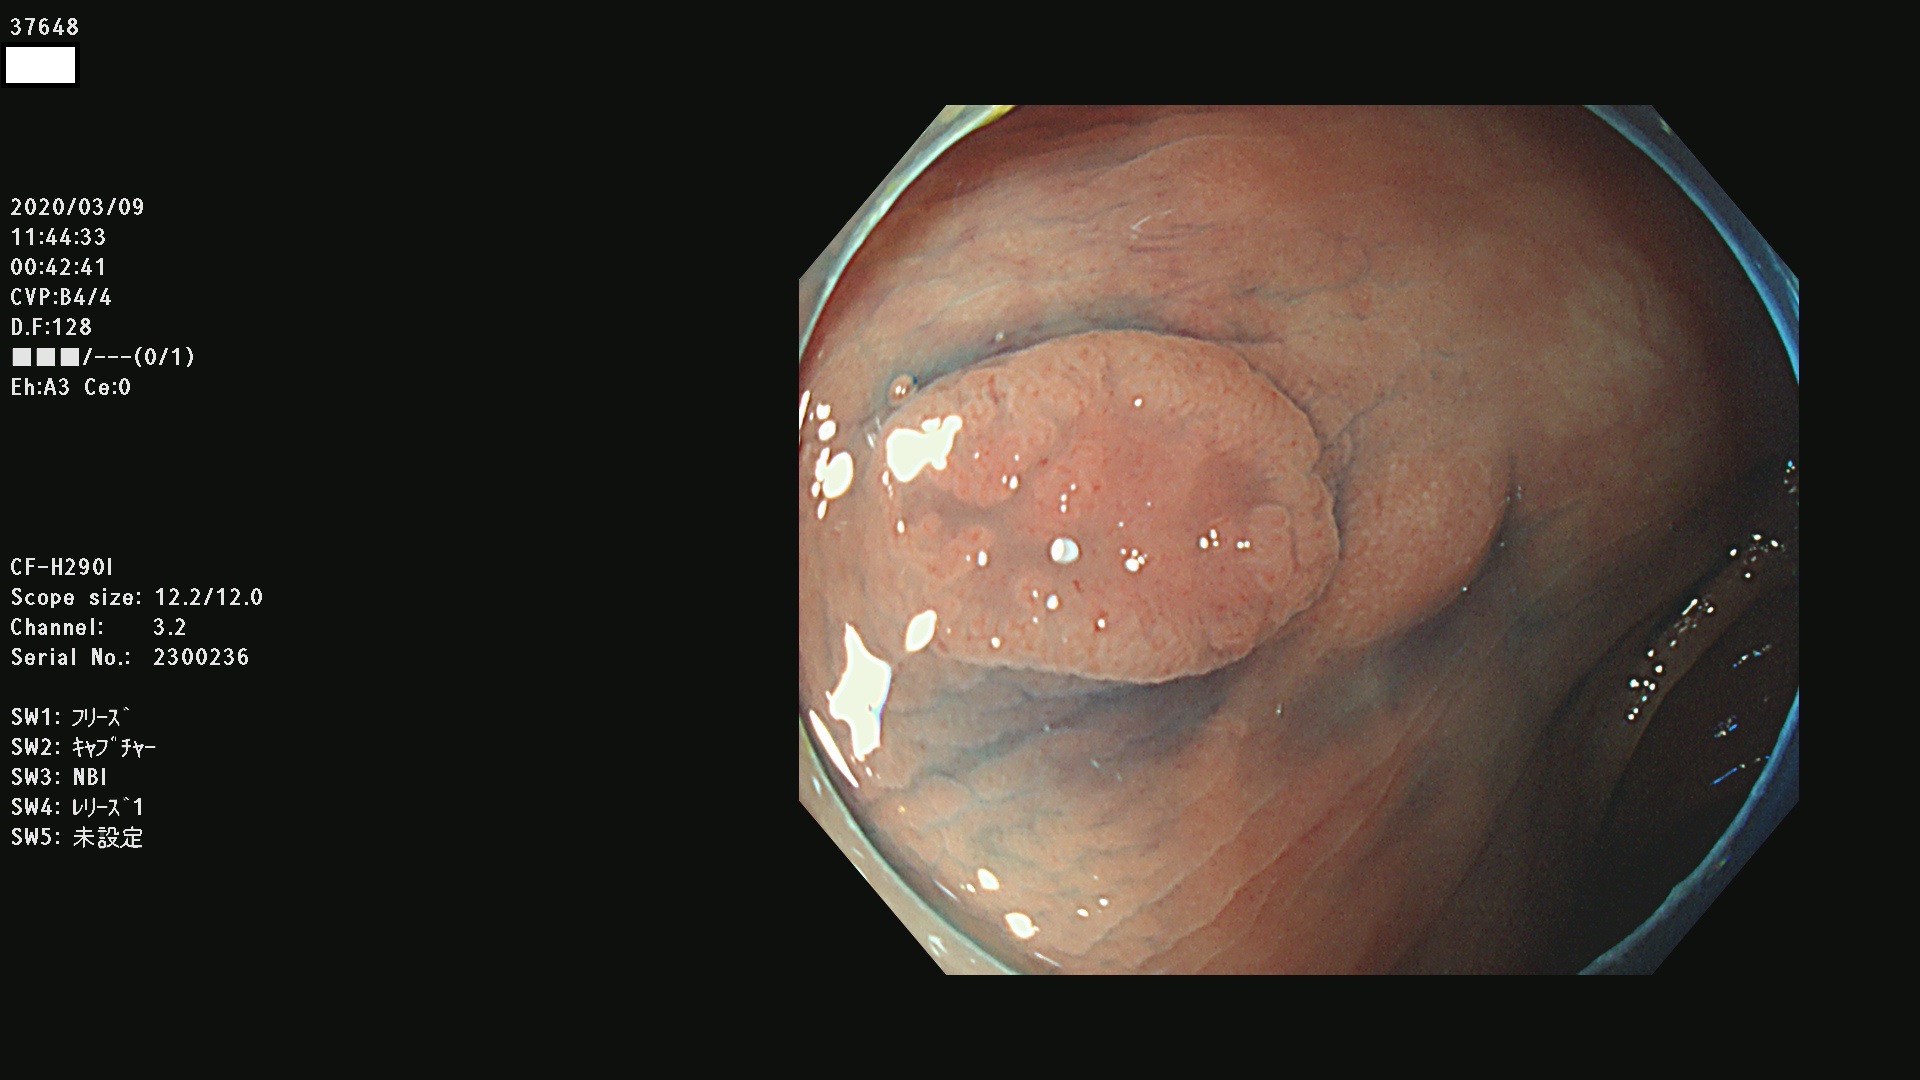

発見困難で危険性の高い平坦型病変(上記100名より抽出)